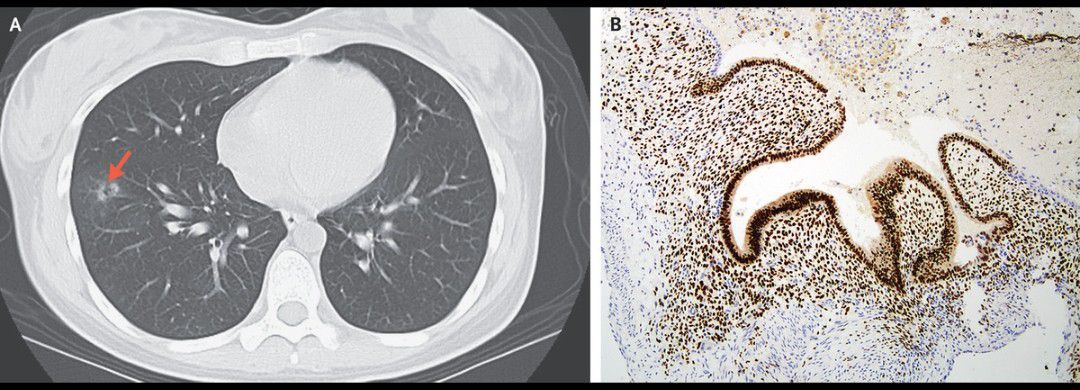

A 26-year-old woman presented to the emergency department with an episode of coughing up blood. During the previous 4 years, she had had intermittent episodes of small-volume hemoptysis coinciding with her menstrual cycles. She had no other abdominal or pelvic symptoms. Her oxygen saturation was 100% while she was breathing ambient air. On physical examination, the lungs were clear. Noncontrast computed tomography (CT) of the chest on the third day of her menstrual cycle showed an 11-mm ground-glass, cavitary nodule in the right lower lobe (Panel A, arrow). A video-assisted thoracoscopic wedge resection was performed, and a reddish-brown lesion was identified. Histopathological analysis revealed endometrial glands and stroma (Panel B), which confirmed a diagnosis of thoracic endometriosis. Catamenial hemoptysis is a rare manifestation of thoracic endometriosis, and both CT and histopathological examination are important for diagnosis. At a follow-up visit 2 years after resection, the patient was symptom-free.